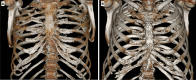

Fig. 4

Three-dimensional images of thoracic wall show chondro-sternal ossification, typically located centrally in females (A) and peripherally in males (B)